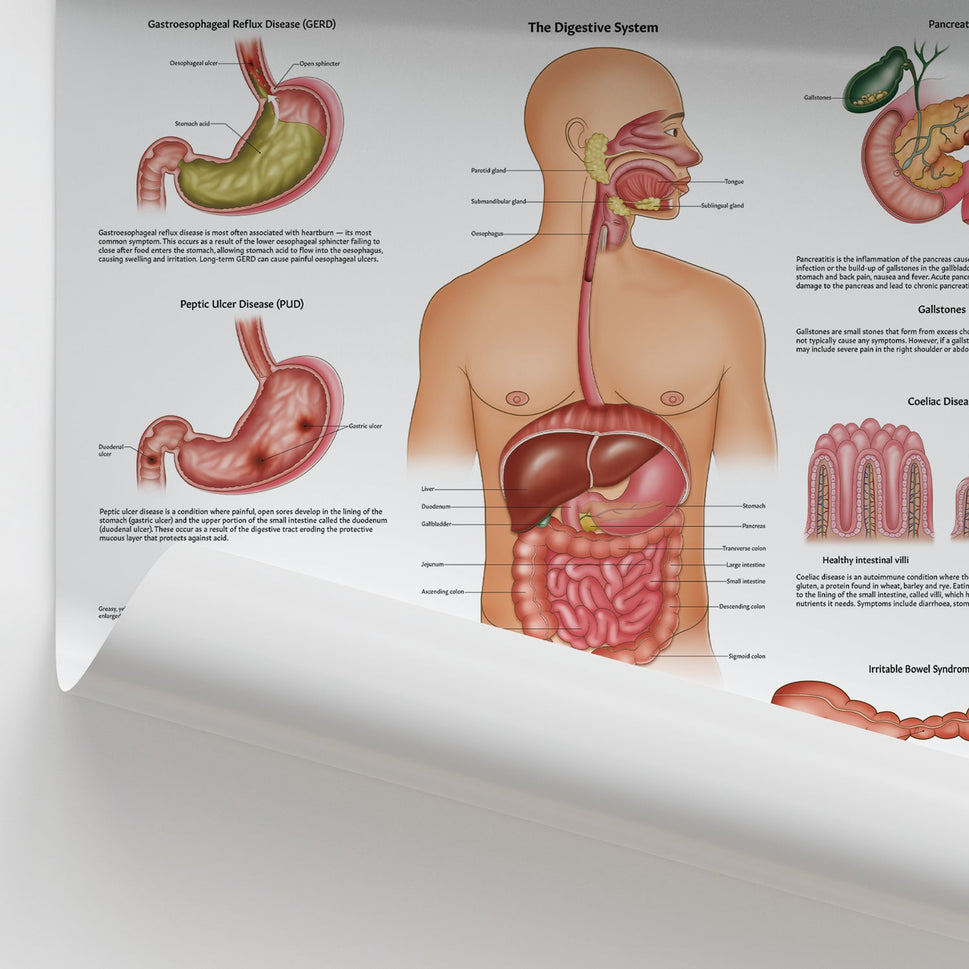

Enhance medical education with our collection of digestive system anatomical models including the stomach, liver, gallbladder, pancreas & colon models. Discover the anatomy of healthy organs as well as common gastrointestinal diseases such as stomach ulcers, gallstones and liver cirrhosis. Our digestive system anatomy posters are ideal for study and patient education.

At AnatomyStuff we stock a diverse range of digestive system anatomical models to suit your training needs. From budget models and affordable medical education posters to highly advanced 3D printed bowel models, you can transform medical training and patient education. As well as our own exclusive collection, we are proud resellers of 3B Scientific, Anatomy Lab, Denoyer-Geppert Science Company, ESP Models, Erler Zimmer and GPI Anatomicals. Explore our exclusive collection of digestive system anatomy charts, posters, fine art prints and digital anatomy study guides. Discover the anatomy of key organs like the liver, stomach, pancreas and bowel as well as the pathophysiology of common conditions like peptic ulcer disease, coeliac disease, IBD and much more. We have anatomy posters suitable for school children all the way up to medical degree level. From a liver anatomy poster to a digital study guide all about common GI disorders, find exactly what you need right here to enhance medical training and patient education.